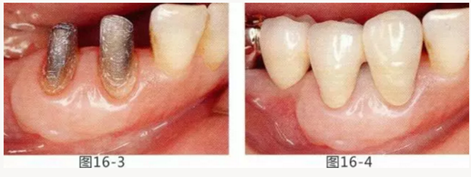

圖16-1 右3,4牙周袋探診值為3~4mm,基本沒有附著齦。右下3部位的系帶也附著在牙頸部附近,由于清潔困難而引發(fā)了炎癥。

圖16-2 由于磨牙部缺失,為了能夠進行固定修復而在右下6位置植入種植體,制作右下3,4,5,6固定橋冠。為了增加基牙右下3,4周圍的附著齦,在實施FGG同時去除系帶。

圖16-3 獲得了足夠附著齦,可以抵抗刷牙等外部刺激。

圖16-4 獲得充分附著齦,易清潔的狀態(tài)。修復體之間的鼓形間隙大小均一也使清潔性得到提升。